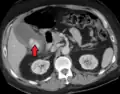

Right upper quadrant abdominal ultrasound is most commonly used to diagnose cholecystitis.[1][26][27] Ultrasound findings suggestive of acute cholecystitis include gallstones, pericholecystic fluid (fluid surrounding the gallbladder), gallbladder wall thickening (wall thickness over 3 mm),[28] dilation of the bile duct, and sonographic Murphy's sign.[13] Given its higher sensitivity, hepatic iminodiacetic acid (HIDA) scan can be used if ultrasound is not diagnostic.[13][14] CT scan may also be used if complications such as perforation or gangrene are suspected.[14]

Acute cholecystitis with gallbladder wall thickening, a large gallstone, and a large gallbladder -